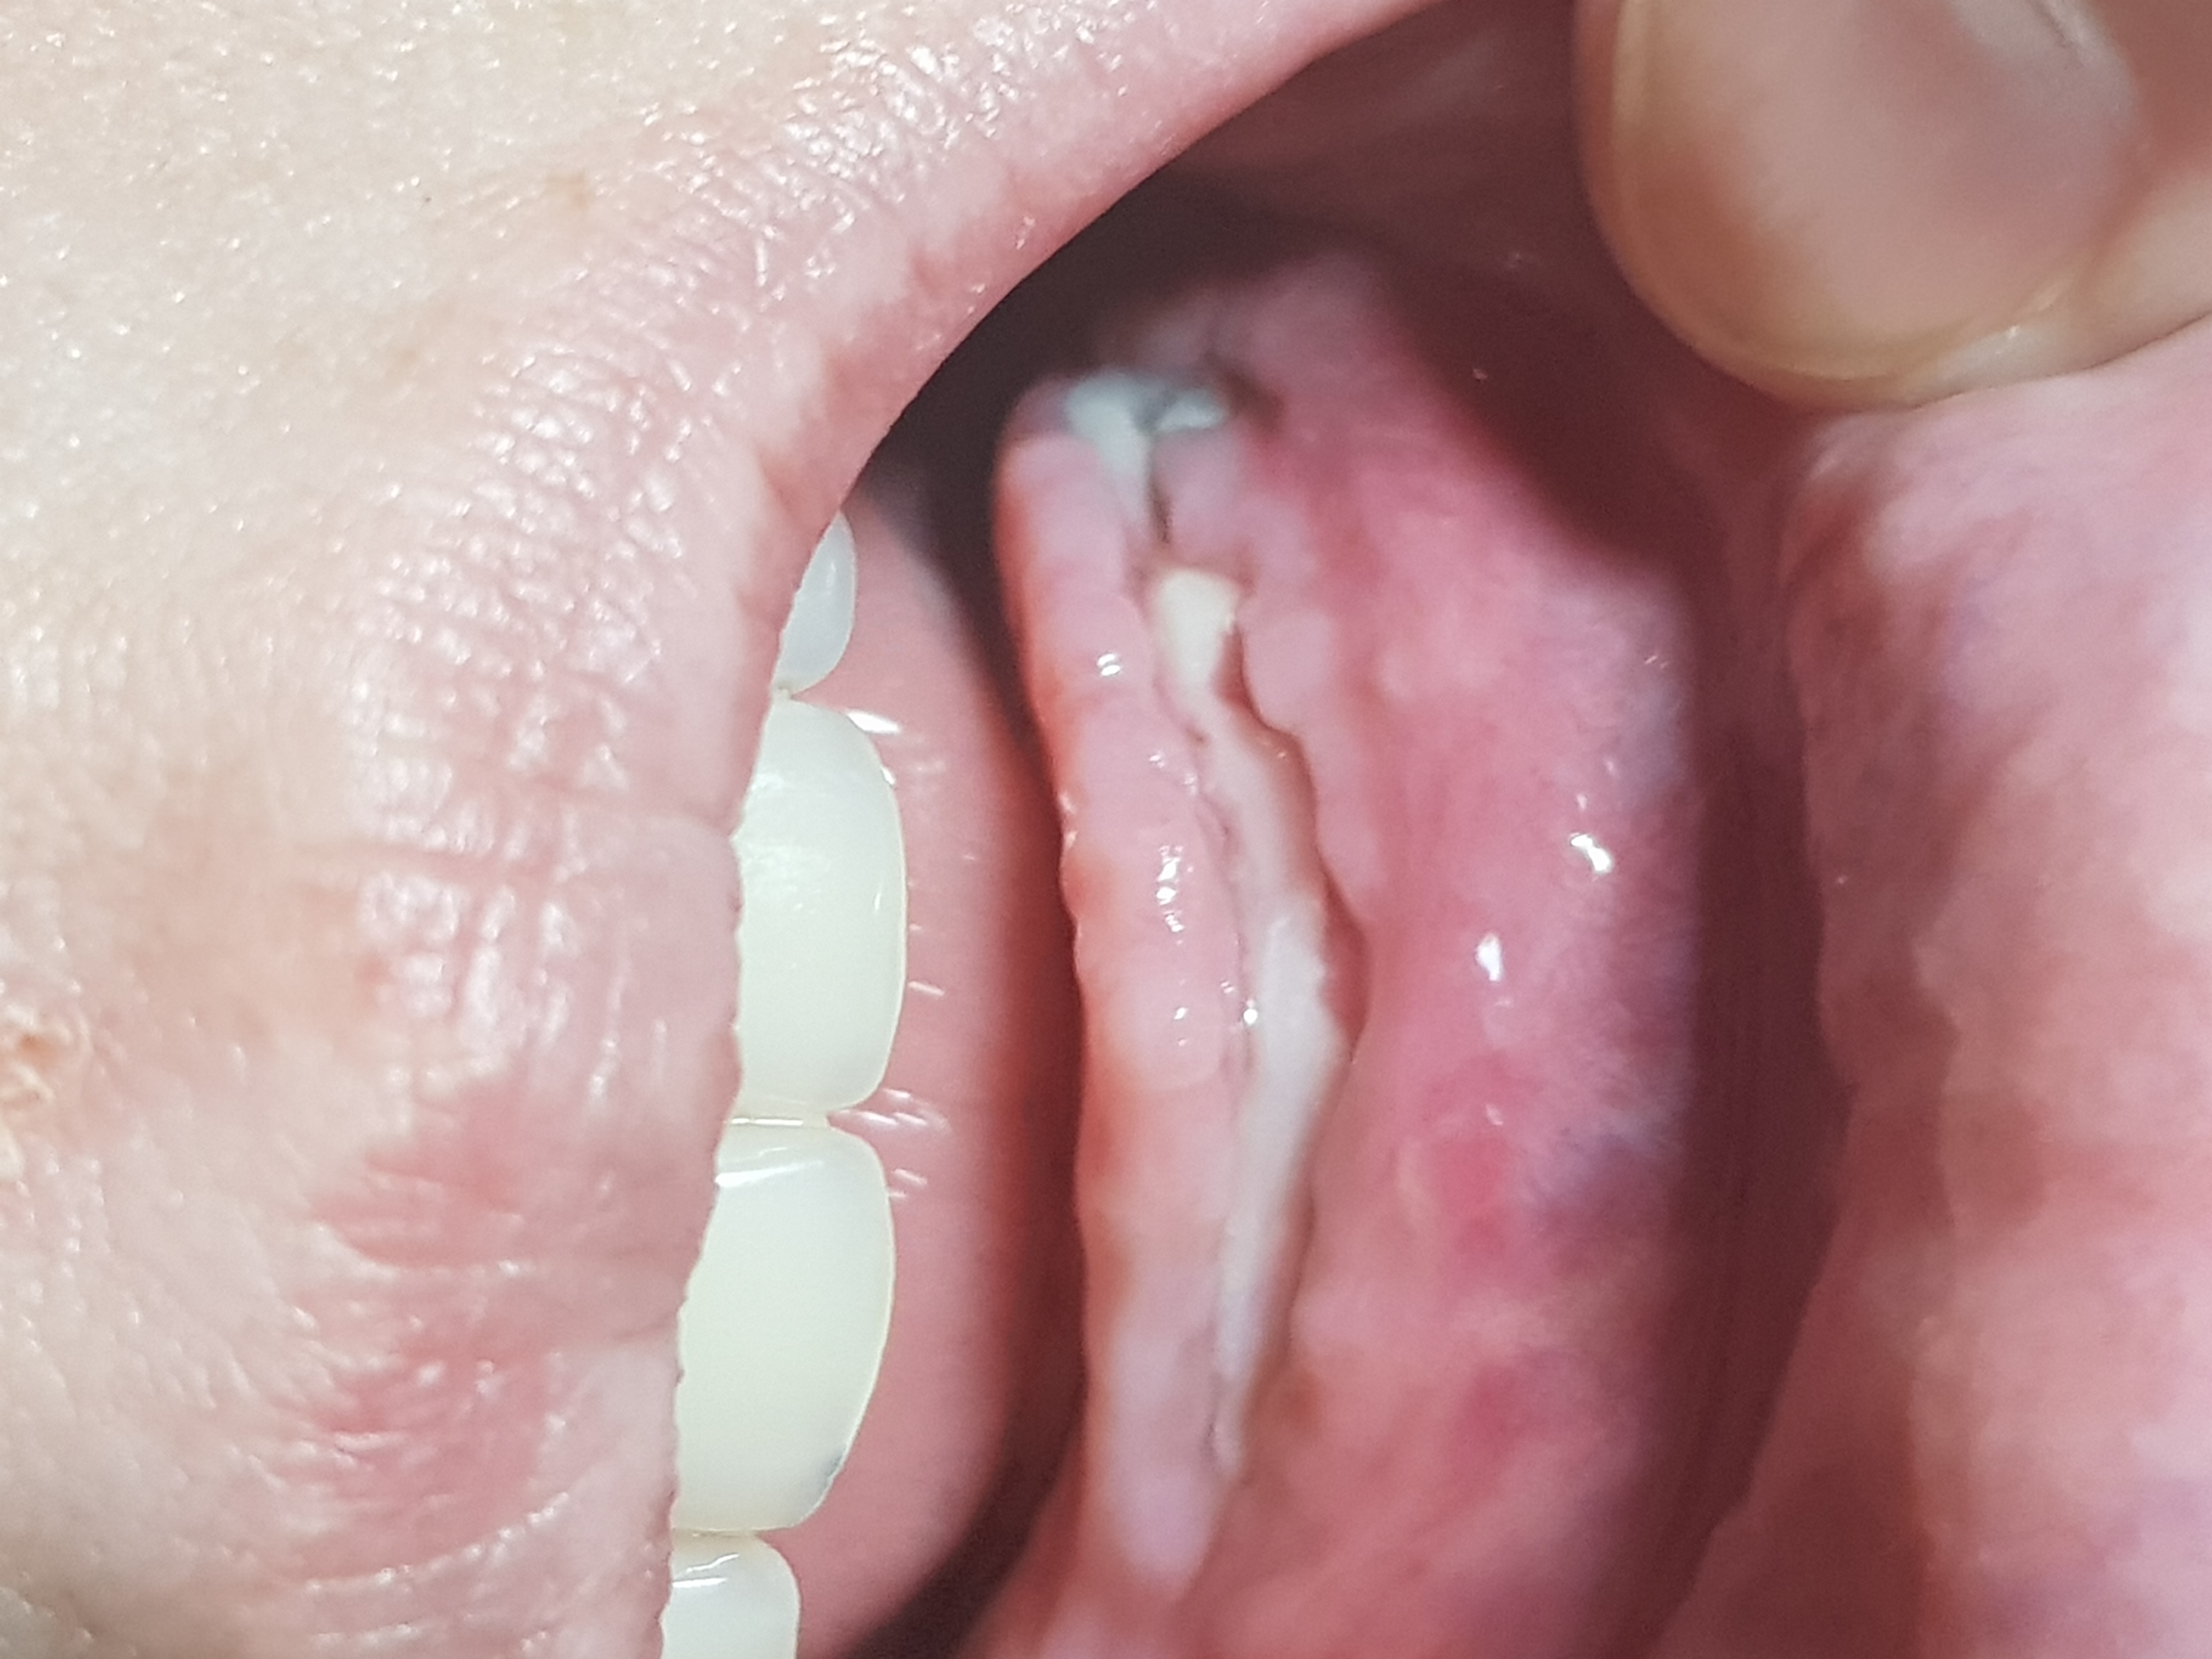

Misschien een rare vraag .deel van me tandvlees is nog open .en is wit van kleur. Is dat normaal. Is dat een teken dat het geneest. Me tandvlees is aan de voor kant open geweest. De helft is gelukkig weer dicht.aan de kant wat nog open is.was meer werk.er moest daar ook meer verdoofd worden.alvast bedankt

Zie foto

Hier nog 1

Wond geneest goed.zie foto …